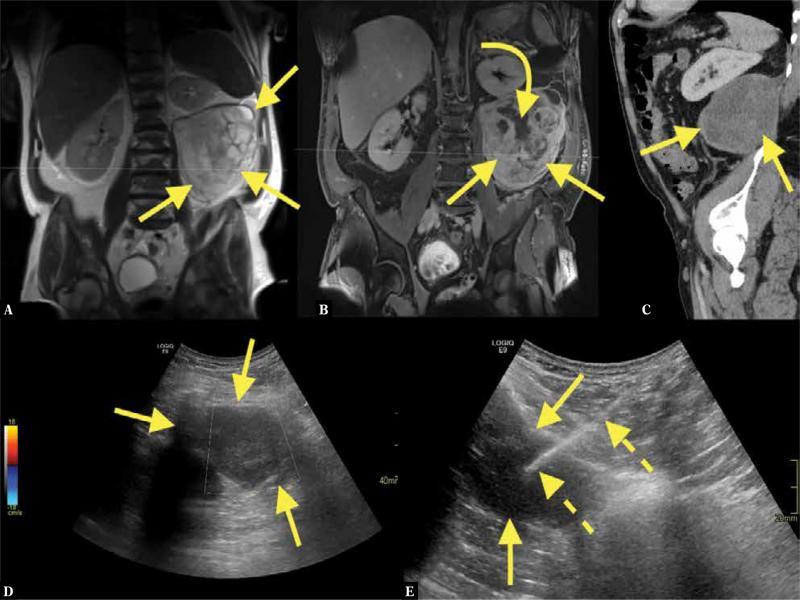

Fig. 3.

A 58-year-old patient presented to the emergency room with left-sided abdominal pain. Imaging revealed an about 17 cm long solid tumor (straight arrows) in the left retroperitoneal space. MRI showed solid and necrotic parts ( A, B ; curved arrow – solid parts). CT showed the solid tumor in the retroperitoneal space on the left side ( C ). The patient was referred for US-CNB with suspected liposarcoma. A coaxial US-CNB was performed ( D, E ). The pathological diagnosis was liposarcoma grade 1